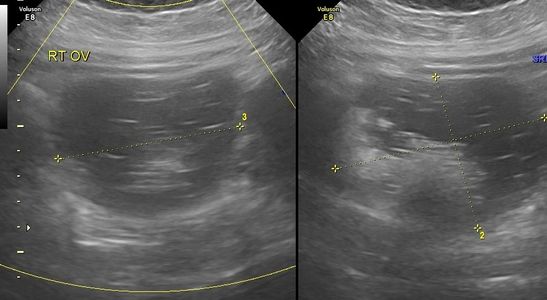

Normal position of an IUD seen on coronal 3D images.

Low and mildly oblique position of an IUD seen on coronal 3D images.